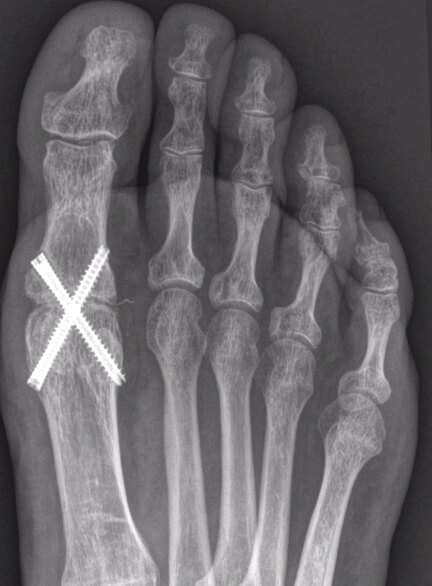

Radiografía de hallux rigidus en pie derecho.

En Centro Atlántico estamos especializados en cirugía mínimamente invasiva del pie, mediante la cual podemos optar por diferentes opciones variando desde técnicas donde se preserve la articulación como la queilectomía o limpieza articular o la descompresión de la articulación hasta procedimientos de fusión articular como la artrodesis, siendo referentes en este tipo de procedimientos a nivel nacional.

La elección del procedimiento depende de la severidad de la condición y las necesidades específicas del paciente.